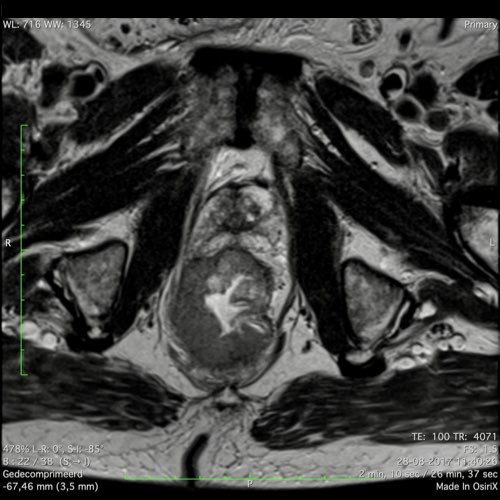

Hình ảnh

Các hình ảnh được cung cấp cho thấy ung thư biểu mô tế bào nhẫn với tình trạng dày lan tỏa thành trực tràng, hình ảnh bia bắn điển hình, và sự xâm lấn mỡ mạc treo trực tràng.